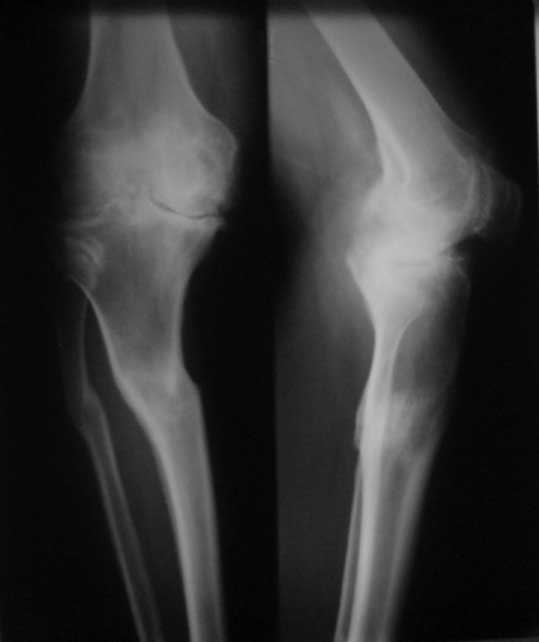

У пациента 50 лет имеется разгибательная контрактура через 8 меспосле ТКА. Уважаемые коллеги. Пациент 8 мес после операции ТКА, в анамнезе – неправильно сросшийся перелом голени, коррекция оси (снимки прилагаются. В настоящее время имеется разгибательная контрактура 10/5/0, на операционном столе было 90/0/5, на момент выписки движения 50/0/0 в надежде на дальнейшую разработку. До эндопротезирования 40/10/0. Глубокая инфекция исключена. Ротация бедренного компонента в норме (по КТ). Вопросы: насколько для такого ограничения критична некорректная установка б/б компонента (я намерял 7 град)? Причина нынешнего состояния, артрофиброз? Какие действия следует предпринять, удаление рубцов, релиз головок 4-главой мышцы? Что-либо другое, ваше мнение? С уважением, Максим Агалаков, Екатеринбург.

Рентгеновский снимок хороший, операция выполнена достойно, надколенник не смущает. Остаюсь на своем мнении, артролиз, если смущает давление надколенника при артроскопии помимо артролиза верхнего заворота, боковых каналов и переднего отдела, дополните латеральным релизом надколенника, чтоб уменьшить натяжение.

Низковат, соласен. Соориентируетесь при операции, если ограничивает движения, перенести бугристость или Z-образная тенотомия связки надколенника, артросокпический артролиз обязательно.